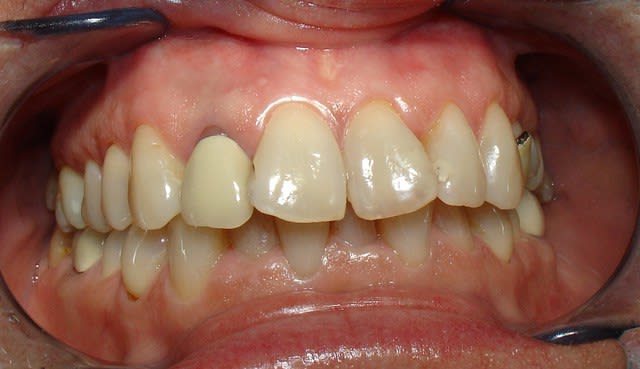

pluton

18/10/2011 à 12h22

joli D57...;-)

çà manque un peu de cas en ce moment...alors en voilà un ptit au passage...

11 avec résorption interne

EII avec MCI sur du dentium (4.5/14) comblement du gap vestibulaire avec du kasios tcp (très constant dans les résultats...et très économique)

pas de photos de chir par contre...j'ai du les effacer par erreur...grrrr...

la prothèse d'usage a été réalisée par ma petite associée...mais j'étais là pour superviser et faire quelques photos...;-)